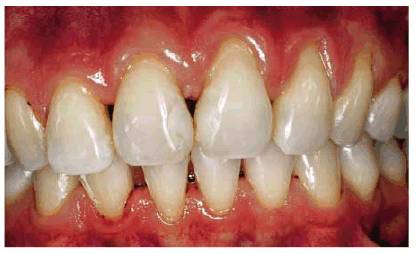

Figure 17-9A shows a 29-year-old female who has

abrasion and gingival recession confined to the anterior left segment,

involving the canine and two incisors on that side. Closer examination revealed

the smooth, rounded nature of the abraded areas (Figure 17-9B). Although she could not recall her

specific age at the time, she reported that she was told by a hygienist that

her brushing technique was improper when she was a teenager. She stated that

she was instructed in brushing and flossing by this hygienist and had noted no

progression of the recession since that time. For the past 8 years, she has

been a patient in the same dental practice, and the clinical charting indicates

that there has been no worsening of the problem. She has been informed about

gingival surgery to correct the defects but has declined since she does not

show her teeth when smiling.

Figure 17-9A: A 29-year-old female with abrasion confined to the maxillary left canine and lateral and central incisors.

Figure 17-9B: Close examination reveals smooth, rounded, abraded areas that are suspected to be the result of improper brushing.